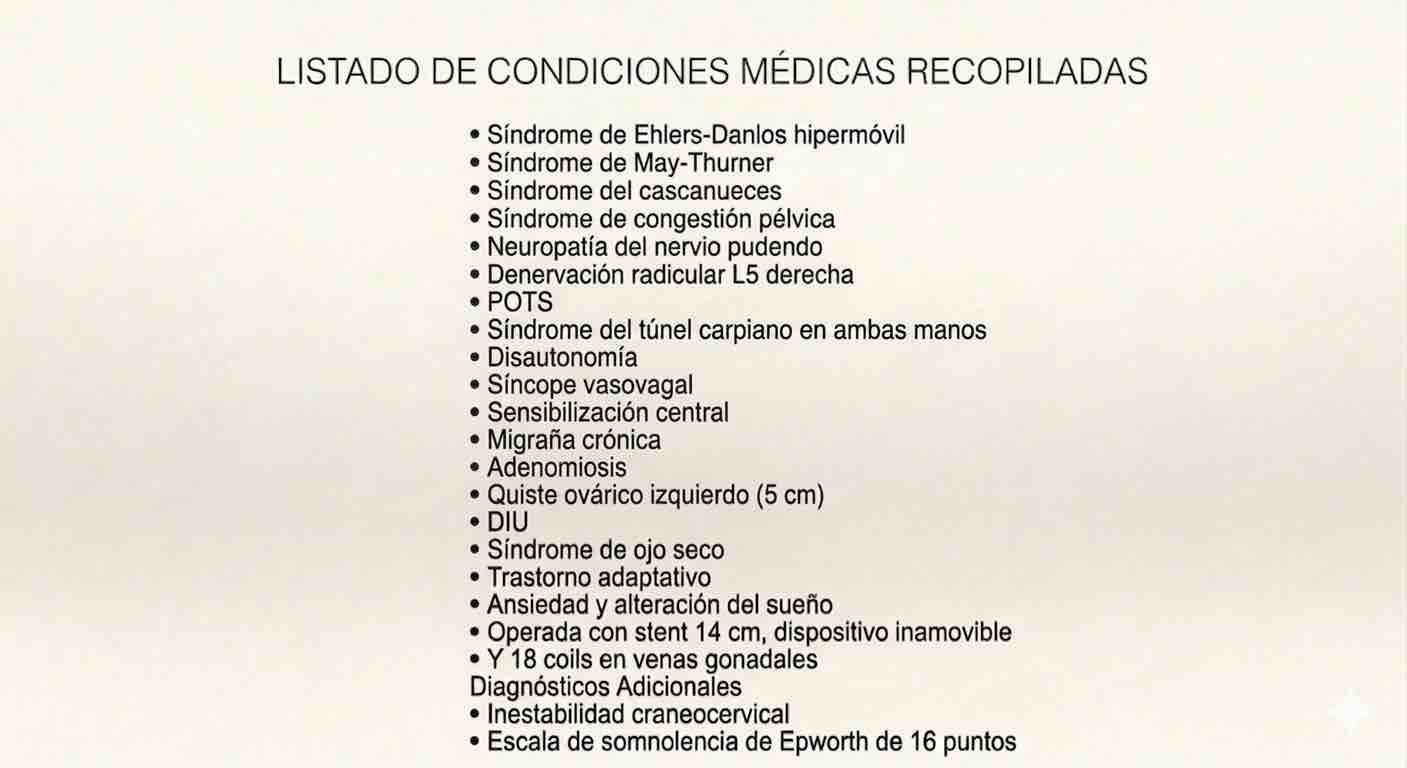

Estoy diagnosticada con un cuadro clínico complejo y raro que combina:

• Síndromes Vasculares Compresivos: (Cascanueces, May-Thurner, Congestión Pélvica) que me causan un dolor insoportable.

• Neuropatías y Radiculopatías: Daño nervioso que afecta mis piernas y zona pélvica, limitando mi movilidad.

• Condiciones Crónicas: Endometriosis profunda, Adenomiosis y Síndrome de Ehlers-Danlos, que agravan todo mi cuadro.

I have been diagnosed with a complex and rare clinical profile that combines:

• Vascular Compressive Syndromes: (Nutcracker, May-Thurner, Pelvic Congestion) that cause unbearable pain.

• Neuropathies and Radiculopathies: Nerve damage affecting my legs and pelvic area, severely limiting my mobility.

• Chronic Conditions: Deep Endometriosis, Adenomyosis, and Ehlers-Danlos Syndrome, which aggravate my entire condition.